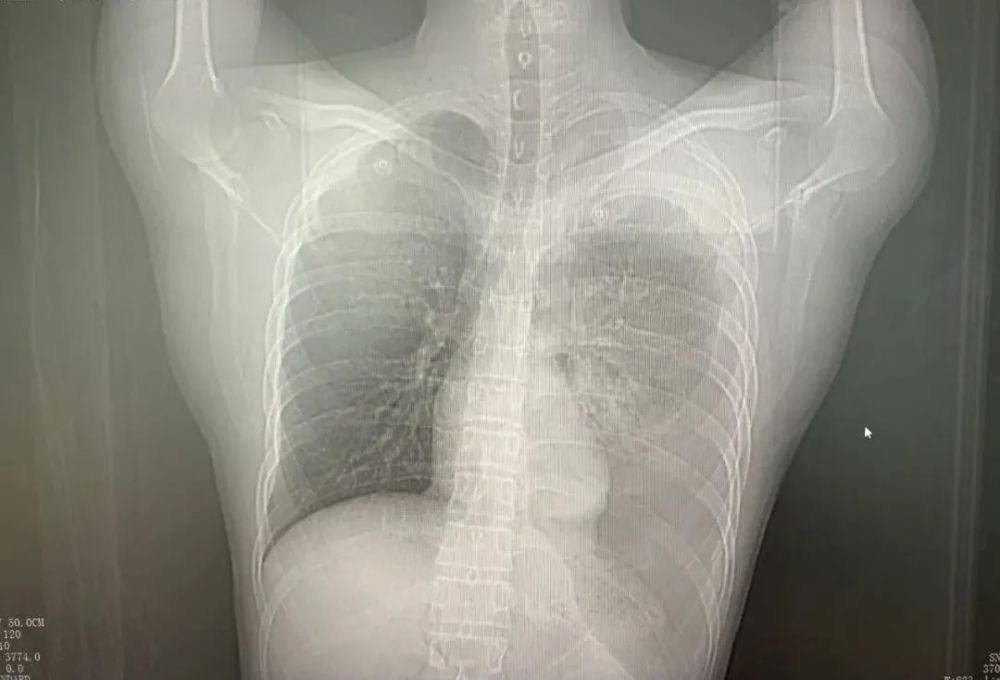

急诊内科医生接诊后,立即查胸部CT,根据CT结果,高度怀疑是自发性血气胸,马上请胸外科聂运祥主任会诊。聂主任仔细为王先生查体,发现其心率达100-110次/分钟,血压仅有100/60mmHg,听诊左肺呼吸音低,结合胸部CT结果,判断为自发性血气胸,胸腔内有大出血,随时有休克风险,要立即急救处理。

肺部CT片